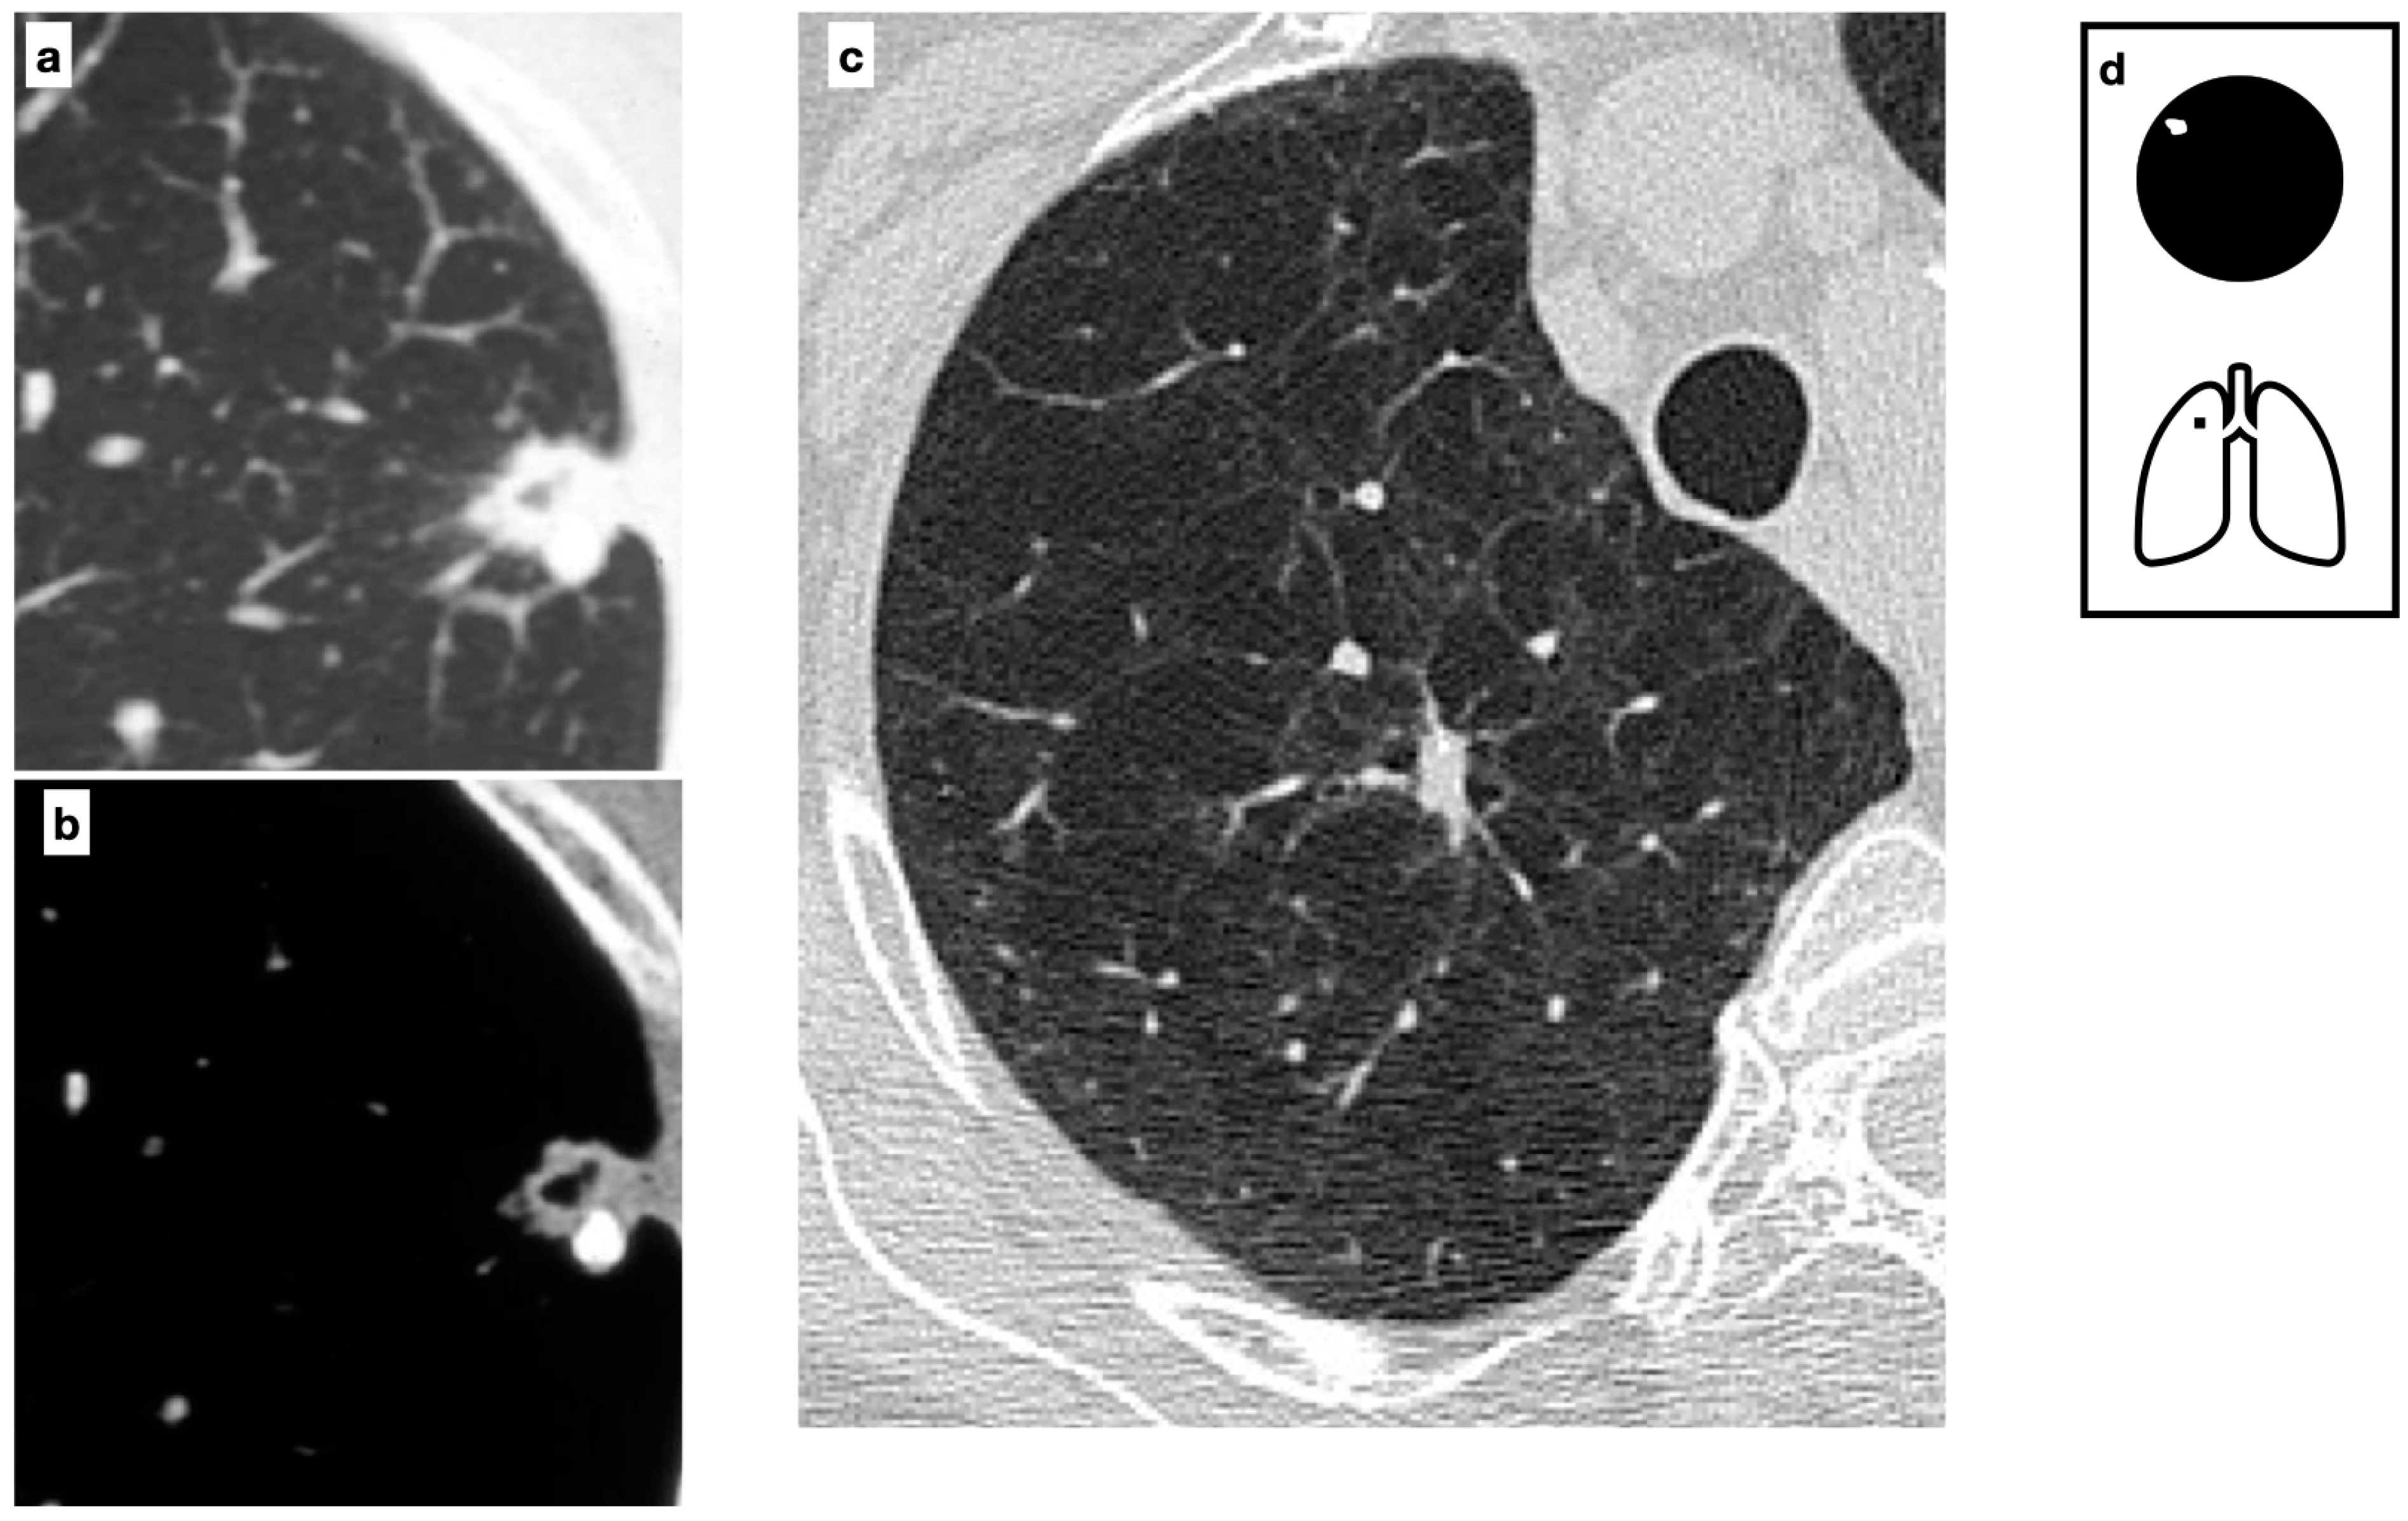

Figure 9.

CT axial images demonstrate a peripheric lung nodule characterized by spiculated margins, small cavitation and an eccentric calcification; this lesion was a biopsy-proven adenocarcinoma (a,b). Heavy smoker patient with severe confluent centrilobular emphysema. HRCT shows a malignant nodule with a small eccentric calcification in the right upper lobe (c). A spiculated nodule with a relatively fast growth rate must always raise the concern for lung cancer in patients with smoking history. Pattern of calcification (d).

The most common calcification patterns in lung cancer are amorphous or punctuate. However, when a malignant lesion engulfs a pre-existing calcified benign nodule, an eccentric calcification pattern may be seen (Figure 9).